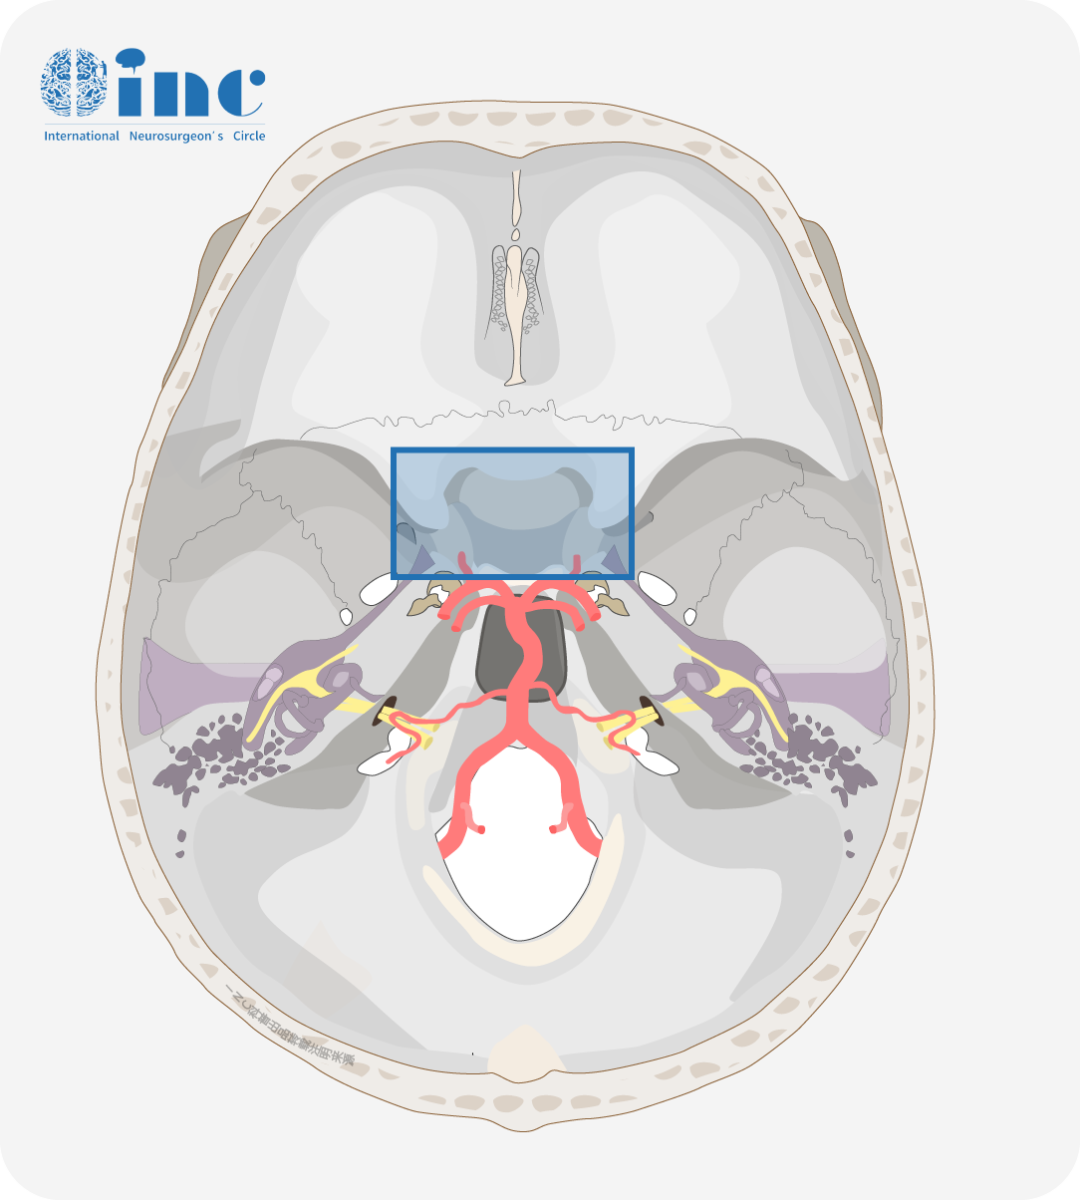

鞍区即蝶鞍区,因形似马鞍而得名,此处集合了垂体、视神经和视交叉、下丘脑等一系列重要的解剖结构,是颅底解剖中较为复杂的区域之一。鞍区其内容纳垂体,其前上方为视交叉,后上方为下丘脑。当鞍区肿瘤向鞍上生长压迫视神经和视交叉时即可引起视力障碍。

图示蓝色框内即为鞍区